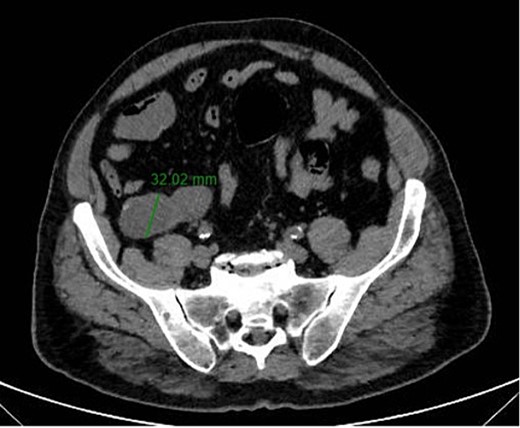

A 67-year-old man presented to our emergency department for abdominal pain occurred about 3 days ago. Past medical history included ischemic heart disease, type II diabetes mellitus, chronic obstructive pulmonary disease, obstructive sleep apnea syndrome, smoking. No history of previous surgery. Laboratory markers showed hemoglobin 13.3 g/dL, leukocytes 8.9 × 109/L, C-reactive protein 11 mg/L. CT scan detected a 7.5 × 3.2 cm diameter suprafluid tubular neoformation in continuity with the caecal fundus, compatible with AM (Figs 1 and 2). A contextual focal wall thickening of 1.1 × 0.5 cm in diameter with slender calcifications was also appreciated. No repetitive parenchymal or peritoneal nodularity had been documented. Colonoscopy showed a rosy and regular mucosa in all colic segments explored up to the cecum, with no detectable pathological lesions.